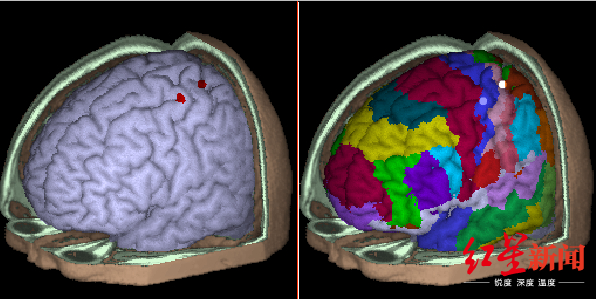

磁共振(MRI):能看形态,还能看组织功能

磁共振成像是利用收集磁共振现象所产生的信号而重建图像的成像技术,简单说就相当于用手摇一摇,让氢质子振动起来,再平静下来,感受一下里面的振动。

伍兵教授介绍,MRI是一种功能成像,比如通过MRI检查大脑,不仅可以检查出大脑形态是否正常,甚至还能判断出大脑在想什么。

优点是与CT相比,它没有放射辐射,没有骨性伪影,能多方面、多参数成像,有高度的软组织分辨能力。

孕妇、婴儿也可以做磁共振检查。